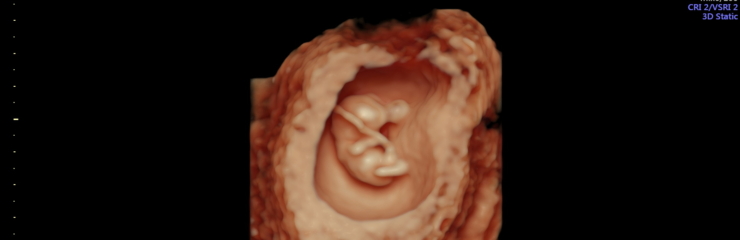

Ultraheliuuringul on loode nähtav. Hakkab moodustuma loote selgroog ning ajul on moodustunud kaks sagarat. Lootel hakkavad arenema käed, jalad ja nägu. 8. nädalal on lootel moodustunud kõik peamised siseorganid. Süda lööb korrapäraselt. Loode on umbes 4 sentimeetrit pikk. Kuni 14.

nädalani mõõdetakse lapse pikkust peast seljani (CLR).

Uuringud:

Rasedust saab tuvastada koduse rasedustestiga. Emakaõõnes saab rasedust diagnoosida 6. rasedusnädala alguses (5+). 6.-7. rasedusnädalal saab ultraheliuuringu abil tuvastada loote südametöö ja välistada emakaväline ja peetunud raseduse. Varajane ultraheli (6.-7. nädalal) on oluline ka embrüo väärarengute diagnostikas. Esimesel visiidil teostatakse järgmised analüüsid – vereanalüüs, analüüsid suguteedest, uriiniproov.